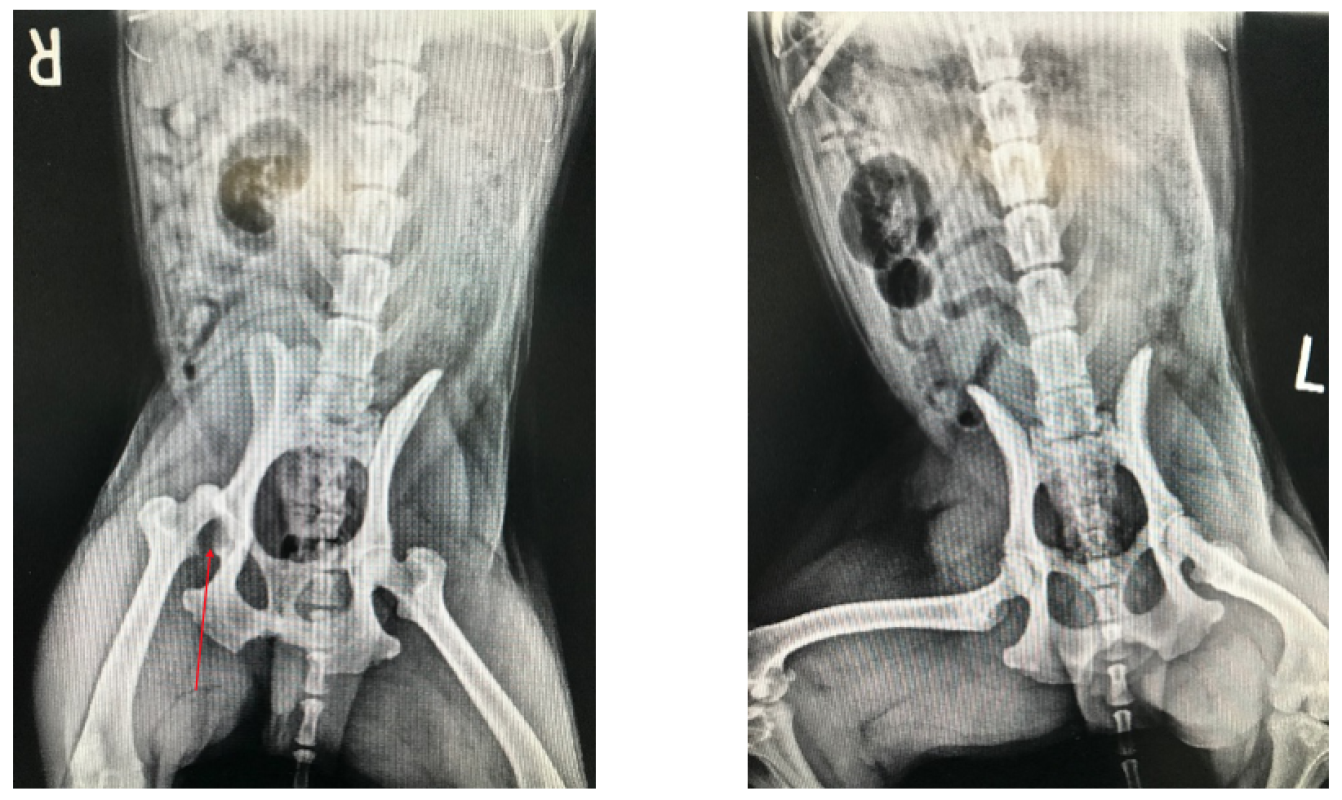

Dr. Bolser sedated Herbie to get a better feel of his hip region. When palpating Herbie’s hip, it was discovered that his femur was displaced from the hip socket, indicated by the lack of hip symmetry. Radiographs confirmed this finding and informed the doctor that his femur was displaced dorsally, or upwards (see image below; red arrow indicates hip socket without femur in appropriate location).

Coxofemoral luxation may be corrected by physical manipulation with medical management, or surgical correction. Physical manipulation has a 50% success rate, thus surgical correction is typically attempted only if physical manipulation is unsuccessful. Herbie was anesthetized and the femur was physically directed back into the hip socket, known as a hip reduction. Radiographs following the procedure confirmed correct placement of the femur (right image below). Herbie went home with his owner with instructions of minimal exercise and NSAIDs (non-steroidal anti-inflammatory drugs) for pain.